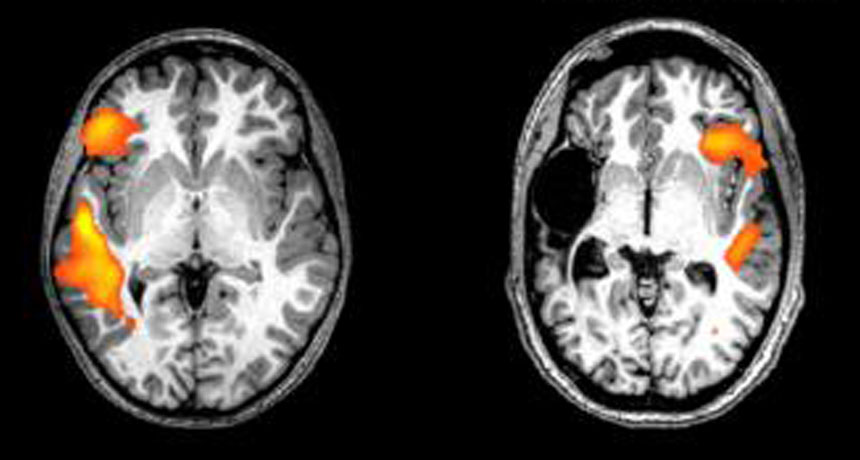

SWITCHING SIDES These fMRI scans show the brain activity of a healthy person (left) and a stroke patient (right) while doing a language-related task. Having a stroke just before or after being born flips key language-processing areas from the left to the right side of the brain, a new study shows.

MRI scans of healthy siblings of the stroke patients showed activity in language centers in the left hemisphere of the brain when the participants heard speech. The stroke patients showed activity in the exact same areas — just on the opposite side of the brain.